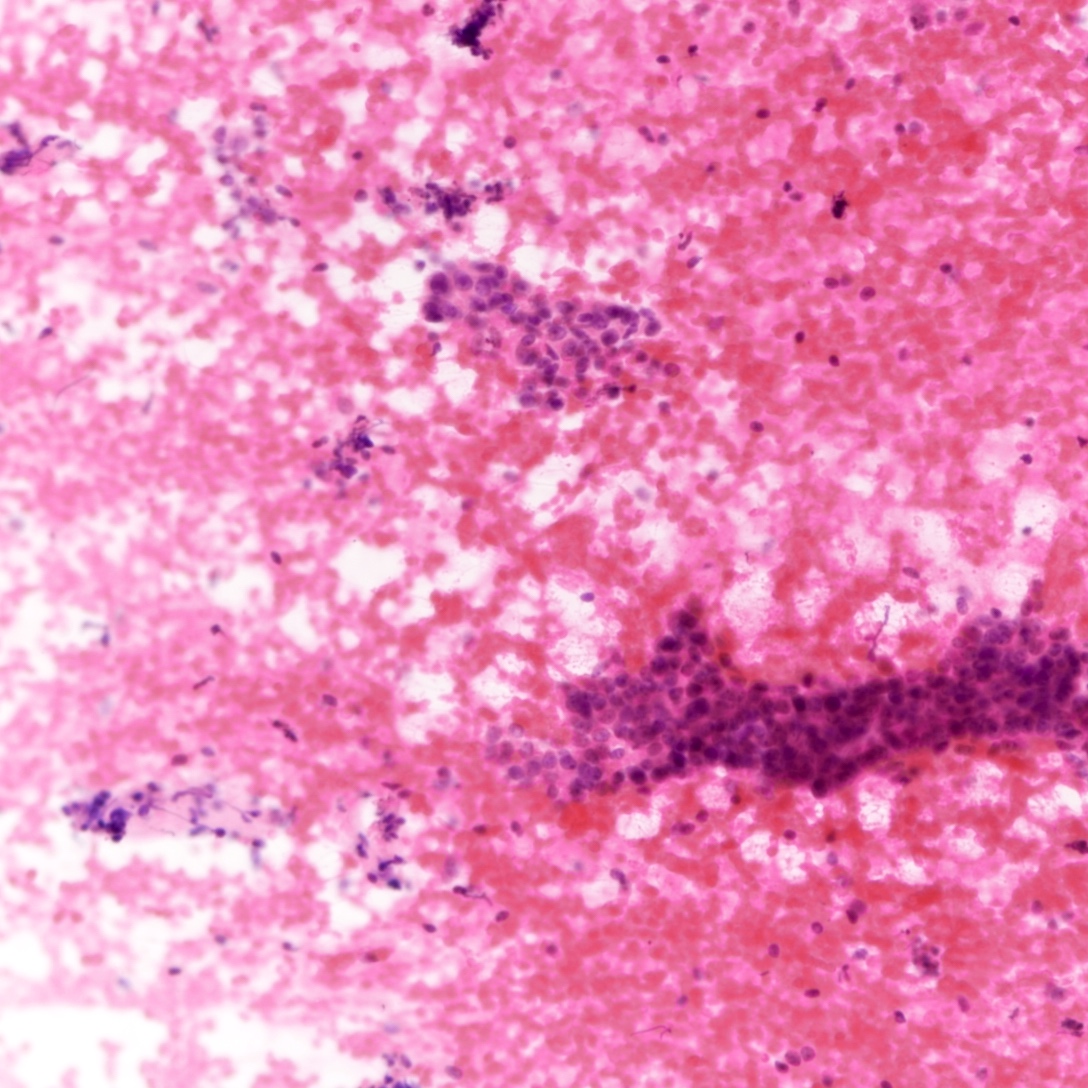

Cytology description

- Tubular fragments (tissue fragments containing multiple tubular structures with or without stroma) is a pathognomonic feature of tubular adenoma (Acta Cytol 2022 Dec 14 [Epub ahead of print])

- Naked nuclei (myoepithelial cells) in the background (N Am J Med Sci 2014;6:219)

- Fibrous fragments scanty (N Am J Med Sci 2014;6:219)

- Epithelial cells arranged in 3 dimensional ball-like structures and probable acinar formations (Acta Cytol 1998;42:657)

- Epithelial cells mostly show bland nuclear features

- Diagnosis based on cytologic assessment only not recommended (N Am J Med Sci 2014;6:219)

Cytology images